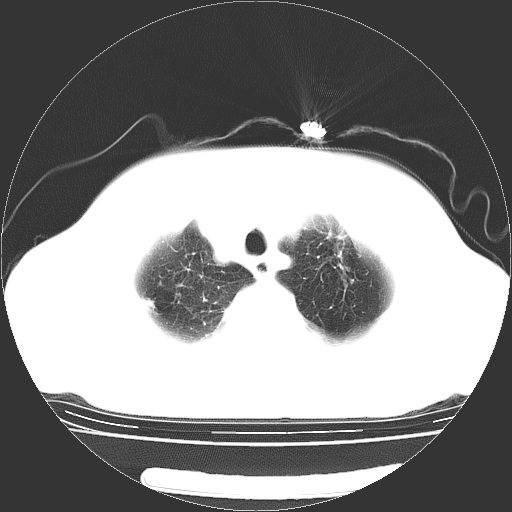

标题: CT23067:女,70岁,咳嗽、咳痰一个月,低热一周。 [打印本页]

女,70岁,咳嗽、咳痰一个月,低热一周。

1.左上肺结核,部分纤维化。右肺中下叶部分肺不张,内见液化、坏死及点状钙化,右中下叶支气管壁增厚、管腔狭窄,见多个点状钙化,结合临床考虑支气管内膜结核,建议痰检查抗酸杆菌并参考血沉。两肺多个小圆点状高密度灶,境界模糊,多考虑结核肺内播散。但本人年龄较大首先应支气管镜检以除外右肺癌。